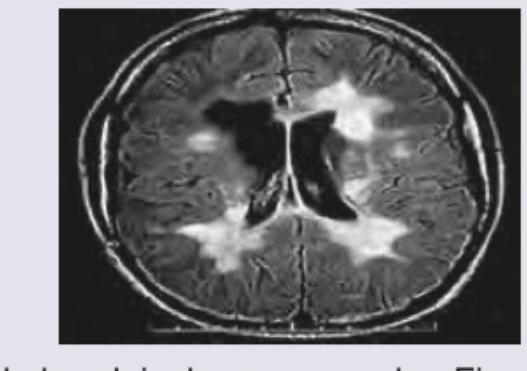

Which of the following drugs is NOT used in the condition shown?

Explanation: ***Intravenous immunoglobulin*** - The image shows a brain MRI with **multiple, hyperintense white matter lesions**, characteristic of **multiple sclerosis (MS)**. IVIG is generally **not a primary treatment** for relapsing-remitting MS (RRMS) or progressive forms of MS, although it might be considered in rare, specific circumstances like highly active disease refractory to standard therapies or in pregnant women where other agents are contraindicated. - While IVIG is used in other autoimmune neurological conditions, its role in MS is **limited and controversial**, and it is not considered a standard disease-modifying therapy. *Methylprednisolone* - **High-dose intravenous methylprednisolone** is the **standard acute treatment for MS relapses**, rapidly reducing inflammation. - It works by suppressing the immune system and reducing the severity and duration of exacerbations in MS. *Fingolimod* - **Fingolimod** is an **oral disease-modifying therapy** approved for relapsing forms of MS, which acts by sequestering lymphocytes in lymph nodes, thus preventing them from entering the CNS. - It is effective in reducing relapse rates and slowing disease progression in MS. *Mitoxantrone* - **Mitoxantrone** is an **immunosuppressant chemotherapy drug** used for worsening relapsing-remitting MS, secondary progressive MS, and progressive relapsing MS. - It is a potent agent reserved for more aggressive forms of MS due to its potential for **cardiotoxicity**.